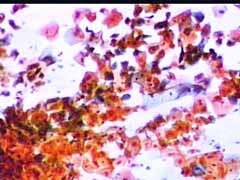

Papanicolaou: Πλακώδη επιθηλιακά κύτταρα κυρίως της επιφανειακήςστιβάδας, περίπου κατά50% και πλέον οξεόφιλα (16η ημέρα κύκλου!) . Ωστόσσο και αρκετά της διαμέσου και της παραβασικής, εν μέρει με διογκωμένους, ανισομεγέθειςαρραιοχρωματικούςδιαυγείςπυρήνεςKοιλοκυττάρωση.Η εικόνα συνηγορεί για δυσπλασία σοβαρού βαθμού.

Λόγω και του κολποσκοπικούευρήματος, μικροβιοψία που κατεδειξε ιστολογικώς CIN III